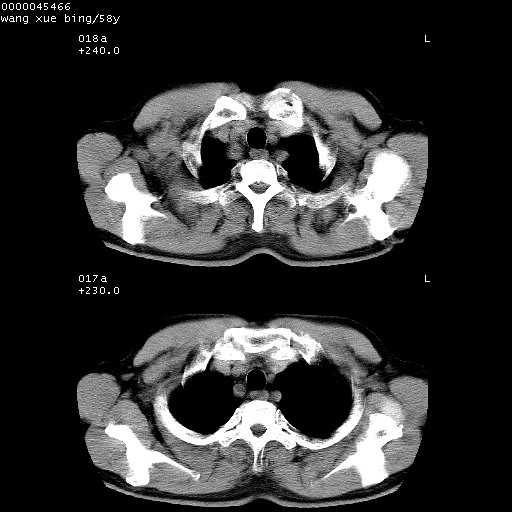

患者 男,58岁。咳嗽、咯血3月余。

胸部cr x线片提示:1)右下肺脓肿。2)右下肺周围型肺癌不排除。建议:行ct扫描检查。

胸部ct轴位平扫(层厚10mm,螺距1.5,重建间隔10mm),图像如下:

右肺下叶团块及不规则空洞,内壁不规则,外缘见粗长毛刺,临近胸膜明显增厚并与病灶关系密切。支持考虑:右肺肺脓肿!建议穿刺病理检查待除外周围型肺癌!